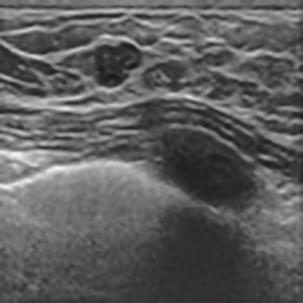

乳腺癌是全球女性最常见的恶性肿瘤之一,准确的病变分割对于乳腺癌的早期诊断与治疗具有重要意义。然而,由于病变形态的多样性以及超声成像机制的复杂性,现有基于深度学习的乳腺超声图像病变分割方法在分割准确性方面仍面临巨大挑战。为进一步提升乳腺超声图像中病变区域的分割精度,该文基于经典U-Net架构,提出了一种新型乳腺超声图像病变分割网络(CWSASKM-BBAM-Net)。首先,在网络中引入逐通道空间自适应选择核卷积模块(CWSASKM),根据不同通道的语义特征为每个空间位置自适应选择感受野大小,以增强多尺度信息的建模能力;然后,引入双向边界感知机制(BBAM),通过融合正向与反向注意力,对目标显著区域及其边界进行协同建模,同时逐步提升对非显著区域与病变区域的区分能力,以进一步强化边界信息的表达;最后,在3组公开乳腺超声图像数据集(BUSI、UDIAT和STU)上开展分割实验。结果表明:该方法在数据集BUSI上的杰卡德指数、精确率、召回率和Dice相似系数分别为71.97%、82.85%、81.40%和80.44%,较次优方法分别提升1.69、1.05、1.28和1.84个百分点;在数据集UDIAT上,这4项指标分别达到78.14%、88.31%、86.73%和86.10%,较次优方法分别提升了2.75、2.04、0.56和2.01个百分点;在外部数据集STU上,该方法也取得了优于其他方法的整体表现。实验结果表明,CWSASKM-BBAM-Net在乳腺超声图像分割任务中展现出更优的整体性能。